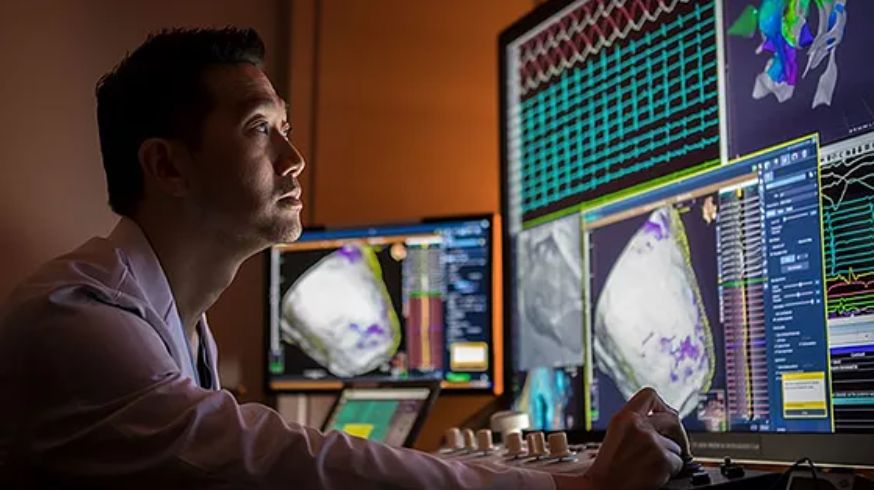

完善和先进的心脏血管诊疗设备

纽约法拉盛血管中心的心脏病专科,拥有最先进的全套心脏血管检测设备。这里的心脏病专科医生为不同的患者提供个性化的心脏检测和诊断。

心脏病医生使用先进的诊疗设备

纽约法拉盛心脏病专科医生 世界一流的治疗技术

纽约法拉盛血管中心心脏病专科医生,熟练运用并精通最先进科技: